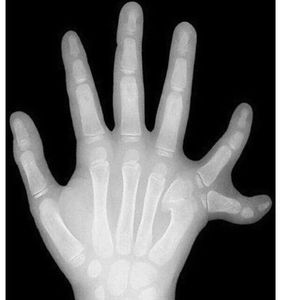

A X-ray of a 6 years old right hand shows polydactylism!

Finger

Six

Polydactylism